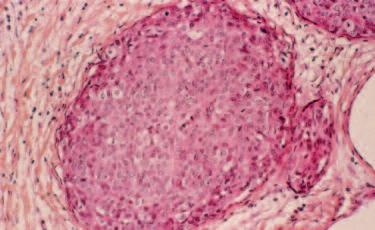

Immagine al microscopio di cellule leucemiche. Le sfere rosse del pacmen rappresentano gli enzimi collagenasi.

La foto nella pagina a fianco mostra una sezione trasversale al microscopio del fegato di un paziente con ‘leucemia linfatica’. Ciascuno dei piccoli puntini viola nella foto è un globulo bianco (in questo caso linfocita) che ha invaso il tessuto del fegato (aree rosa).

Considerando l’enorme quantità di questi puntini viola e il numero di enzimi che assimilano il collagene che ciascuno produce, è facile prevedere l’ingente distruzione del tessuto connettivo e il danno apportato all’organo da questo tipo di cancro.

Immagine al microscopio della leucemia linfatica

Globuli bianchi affetti di cancro (linfociti) invadono il fegato L’enorme quantità di collagenasi prodotte da queste cellule distruggono l’organo e causano insufficienza epatica.